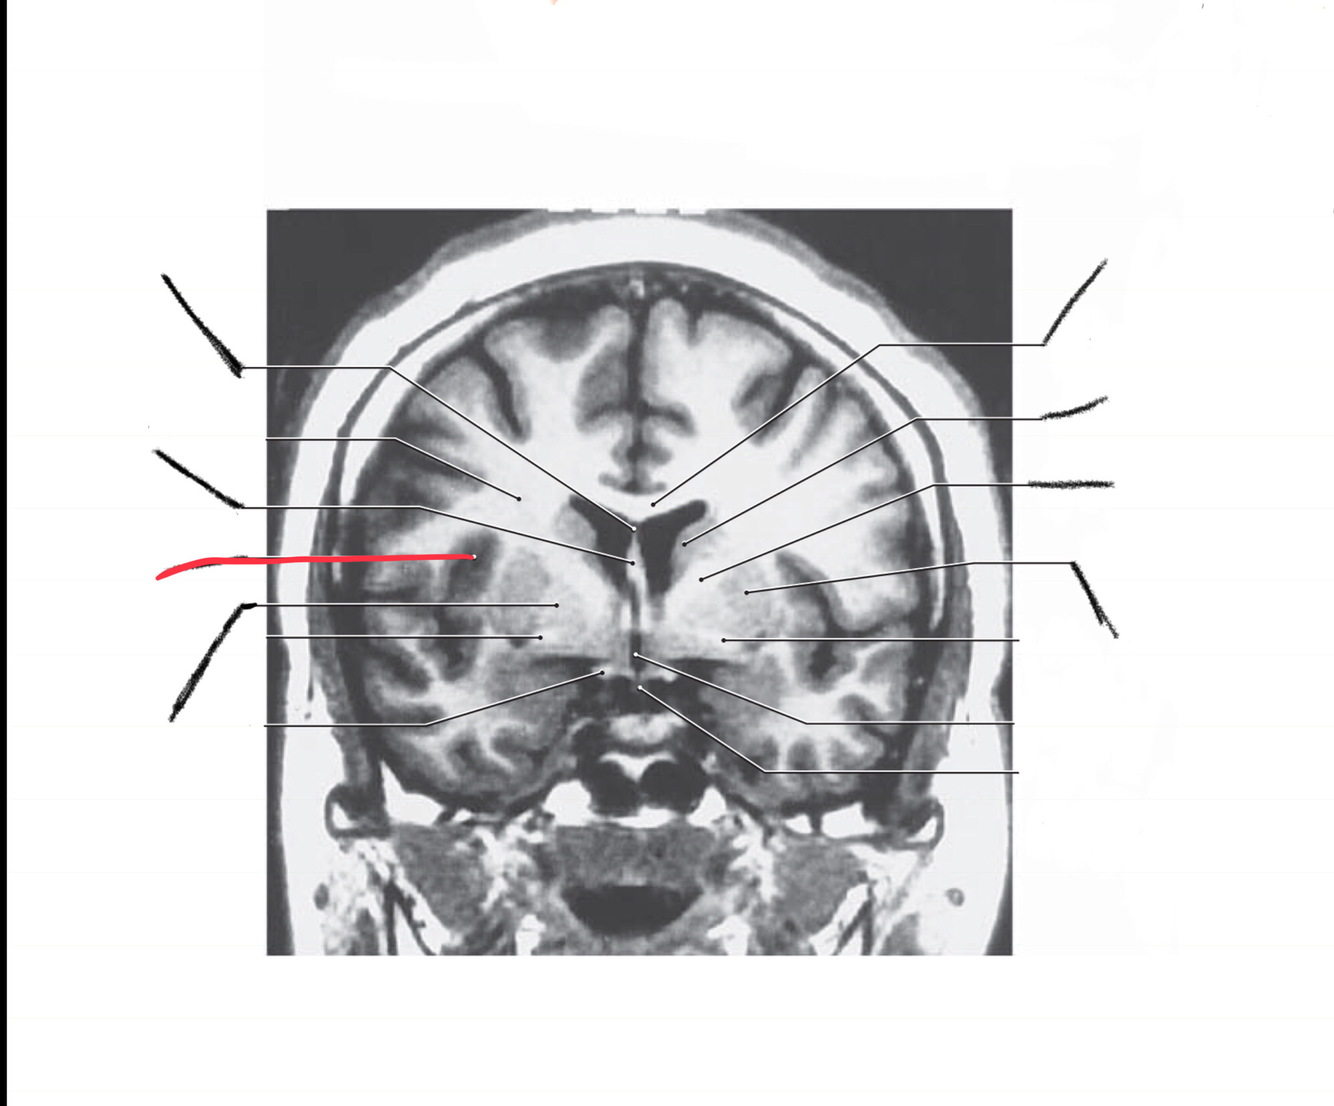

The structure indicated by the red line is?

The structure indicated by the red line is? BONUS: SYMPTOMS IF THERE IS A LESION

motor spatial and directed movements (role in parkinsons?)

Bonus: Split Brain. L and R can’t communicate. Remember the test he did in class where he made us wave? Diagnose like that b/c wernickes is on left side so you cant wave ur left

motor problems